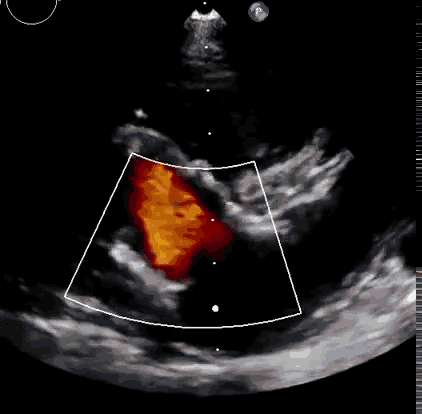

本次臨床前研究經(jīng)右側(cè)頸靜脈置入LuX-Valve Plus輸送系統(tǒng)可調(diào)彎鞘管,在DSA及超聲引導(dǎo)下將人工三尖瓣瓣膜植入到原有三尖瓣位置,利用獨(dú)特的錨定技術(shù)將人工瓣膜支架可靠固定在預(yù)定的位置。

上海中山醫(yī)院葛均波院士、錢菊英院長(zhǎng)、周達(dá)新教授、潘文志教授、潘翠珍教授、李偉教授共同完成此次臨床前研究。術(shù)后葛均波院士對(duì)Lux-Valve Plus的器械操作性能給予了高度評(píng)價(jià),DSA和超聲影像也顯示出在本次研究中Lux-Valve Plus的安全性和有效性俱佳。